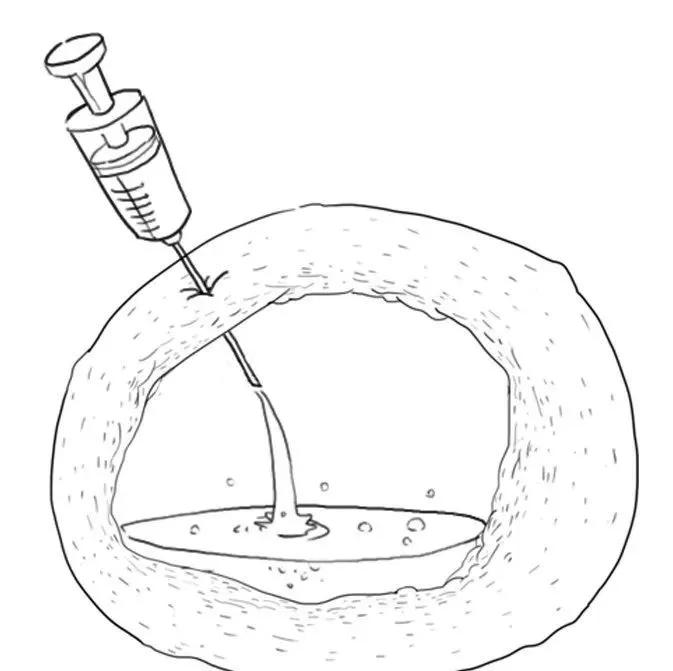

4、介入治疗:B超引导下巧囊穿刺,抽出囊液

这种方法较多用于复发的且有生育要求的年轻患者。或者用于较大的巧囊,抽吸囊液后配合药物治疗,以期在后面手术中缩小囊肿体积,减少术中卵巢皮质的丢失。

将它冲洗干净。

入硬化剂,使内膜宝宝脱水坏死。